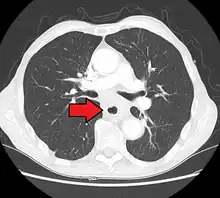

Esophageal cancer as shown by a filling defect during an upper GI series

Although an occlusive tumor may be suspected on a barium swallow or barium meal, the diagnosis is best made with an examination using an endoscope. This involves the passing of a flexible tube with a light and camera down the esophagus and examining the wall, and is called an esophagogastroduodenoscopy. Biopsies taken of suspicious lesions are then examined histologically for signs of malignancy.

Additional testing is needed to assess how much the cancer has spread (see § Staging, below). Computed tomography (CT) of the chest, abdomen and pelvis can evaluate whether the cancer has spread to adjacent tissues or distant organs (especially liver and lymph nodes). The sensitivity of a CT scan is limited by its ability to detect masses (e.g. enlarged lymph nodes or involved organs) generally larger than 1 cm.[43][44] Positron emission tomography is also used to estimate the extent of the disease and is regarded as more precise than CT alone.[45] PET/MR as a novel modality has shown promising results in preoperative staging with fair feasibility and good correlation in comparison to PET/CT. It can enhance tissue differentiation with lowering the radiation dose to the patient.[46] Esophageal endoscopic ultrasound can provide staging information regarding the level of tumor invasion, and possible spread to regional lymph nodes.